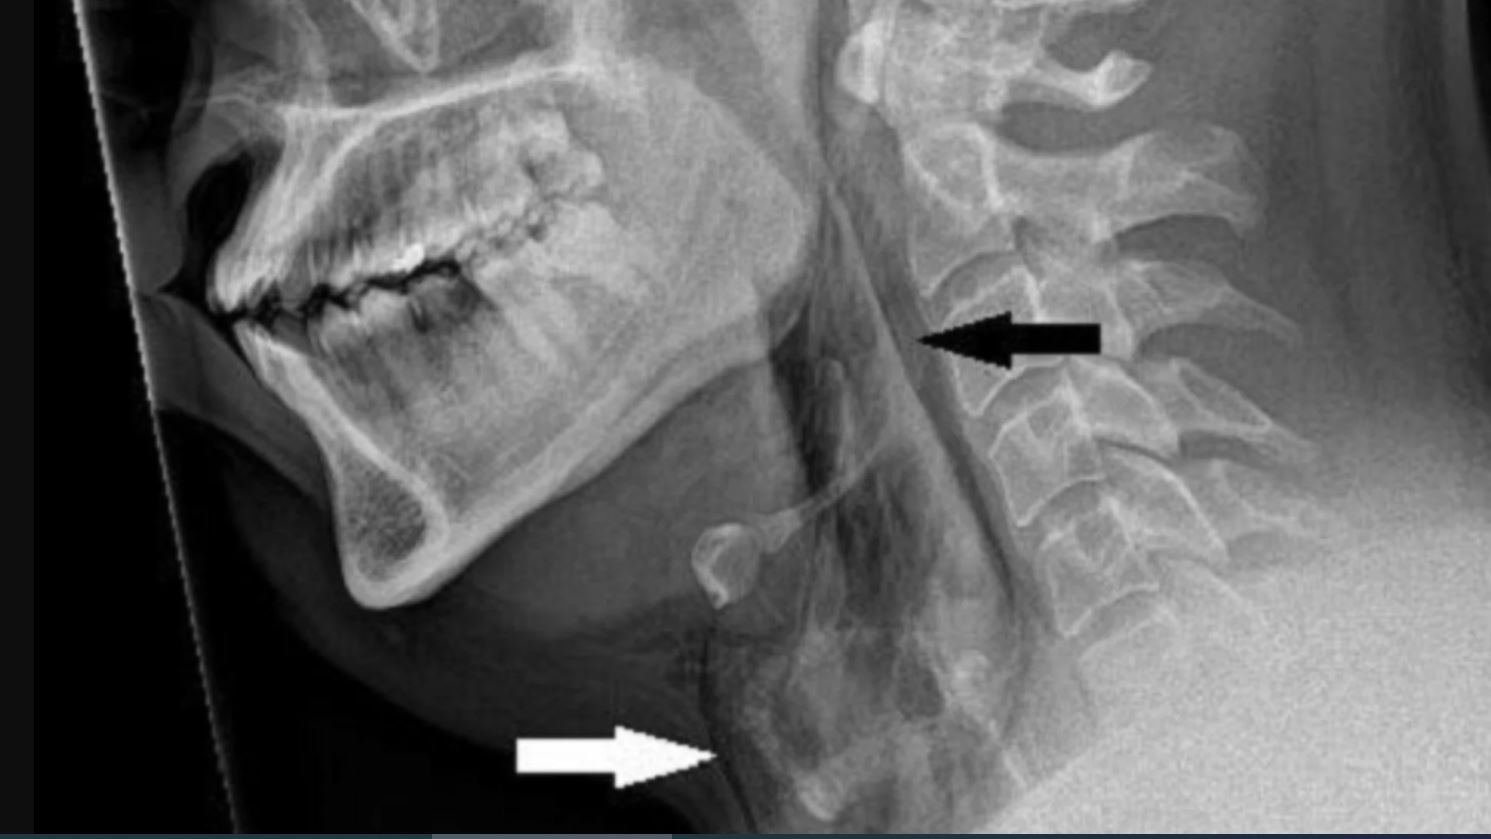

وكشفت عمليات المسح بحسب (RT) عن تمزق في القصبة الهوائية، وفي الحالات الشديدة، يمكن أن تؤدي تمزقات القصبة الهوائية إلى تضييق المسالك الهوائية، ما يسبب مشاكل في التنفس تهدد الحياة.

وقال الأطباء: "نشتبه في أن القصبة الهوائية مثقوبة بسبب التراكم السريع للضغط في القصبة الهوائية أثناء العطاس مع أنف مسدود وفم مغلق".